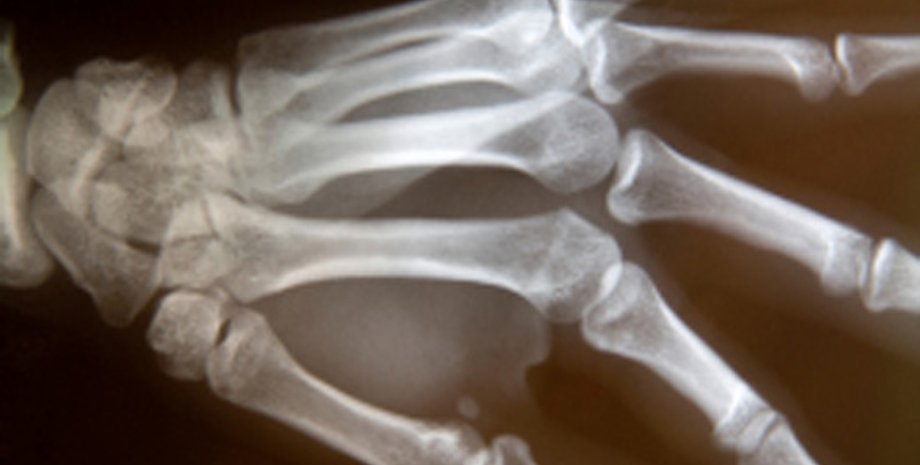

На первое место британцы поместили открытие рентгеновского излучения и изобретение использующих его медицинских приборов. Этот вариант поддержали 10 тысяч опрошенных. Второе место заняло открытие пенициллина. На третье место жители Великобритании поместили определение структуры ДНК. Далее следуют создание корабля "Аполлон-10" и баллистической ракеты "Фау-2", изобретение паровоза, вычислительных машин, парового двигателя, массового автомобиля и телеграфа. Исходный список изобретений был составлен сотрудниками Музея науки.